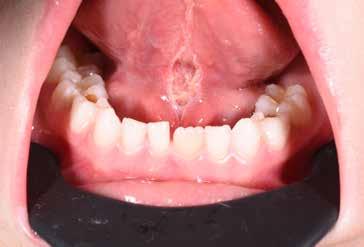

B.A. Paziente di cinque anni, in II Classe scheletrica, con deep-bite deglutizione atipica, contrazione lieve dell’arcata superiore, presenza di muro anteriore. Il paziente presenta un frenulo linguale patologico a tal punto da creare una grave ipomobilità linguale.

La sequenza terapeutica ha previsto seguenti step:

• frenulectomia laser;

• logopedia;

• terapia elastodontica al fine di ripristinare la corretta crescita scheletrica.

In questi casi è fondamentale l’intervento precoce; sarebbe stato opportuno trattare il frenulo linguale già alla nascita per evitare le complicanze scheletriche, dentali e funzionali ad esso associate.

Fig. 29 > Immagine intra-orale frontale.

Fig. 30 > Immagine occlusale inferiore con dettaglio del frenulo linguale.